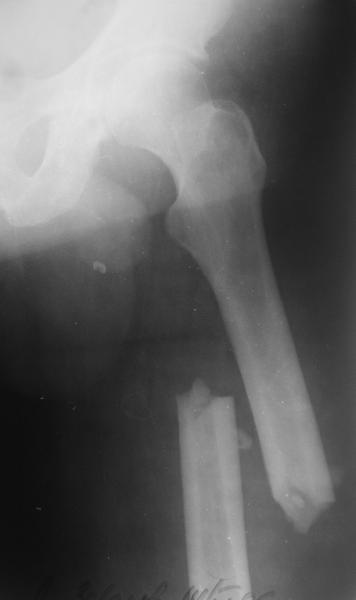

Александр Николаевич, как не прискорбно, я практически заканчивал эту операцию.

Изначально у оперируещего хирурга были только теоретичесике представления о ЗИМО с блокированием, планировался компрессионно-динамический остеосинтез стержнем S2 (Stryker).

Во время операции ни стол ортопедический,ни ДРУ не применялось (думалось, что сделают все на руках!)

Изначально была выбрана не правильная точка введения стержня, в связи с чем в конце, я подчеркну, в конце операции произошло из-за напряжения между прокимальным концом канала бедра и стержнем разрушение в/3 бедра.

Проволока наложена потому, что при введении штифта не прошли эту зону римером и произошли сколы на концах отломков.

Под ЭОП во время операции такого смещения не было. Мы бы конечно не отпустили этого больного с такой картиной (сами бы что-то сделали или к вам отпр).

Почему не сделали R-gr? Все банально для таких больниц как наша - не работал R-аппарат в течении 3х недель.(я сам увидел эти снимки у вас)